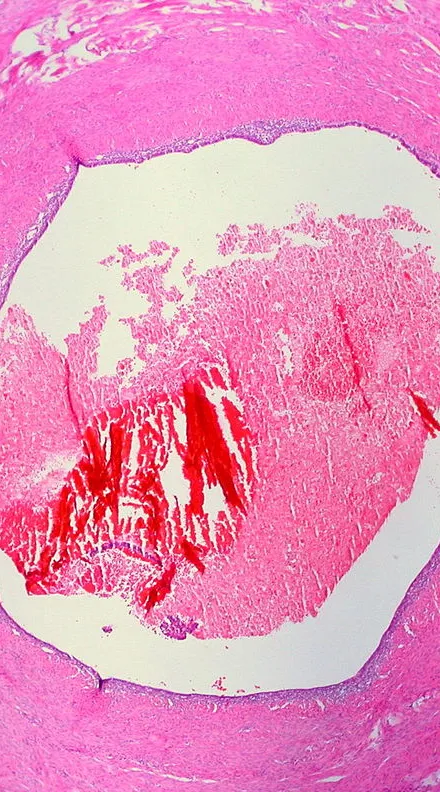

In this episode of our endometriosis mini-series, we’re looking at the latest research being done into endometriosis diagnoses and treatment. We spoke to over a dozen researchers at the Endometriosis CaRe Centre at the University of Oxford about their ongoing work and how it could change the care endometriosis patients receive.

190 million people in the world have endometriosis. But despite how widespread the condition is, many people find themselves waiting years for a diagnosis and struggling to find support. In this episode, we’re chatting with the folks at Endometriosis UK about the diagnostic journey, support services, and how to advocate for yourself if you think you may have endometriosis. This series is funded by the Wellcome Center for Human Genetics.

190 million people in the world have endometriosis. So why do we know so little about it?

In this endometriosis mini-series, we’ll explore the condition—from ancient treatments to cutting-edge research. In this episode, we look at 2,000 years of history to explore how people with endometriosis symptoms were treated (and often dismissed). Then we talk to Dr. Camran Nezhat, a pioneer and leading practitioner in the field of minimally invasive surgery, who shares his 40-year journey advocating for endometriosis patients and advancing endometriosis research and awareness.